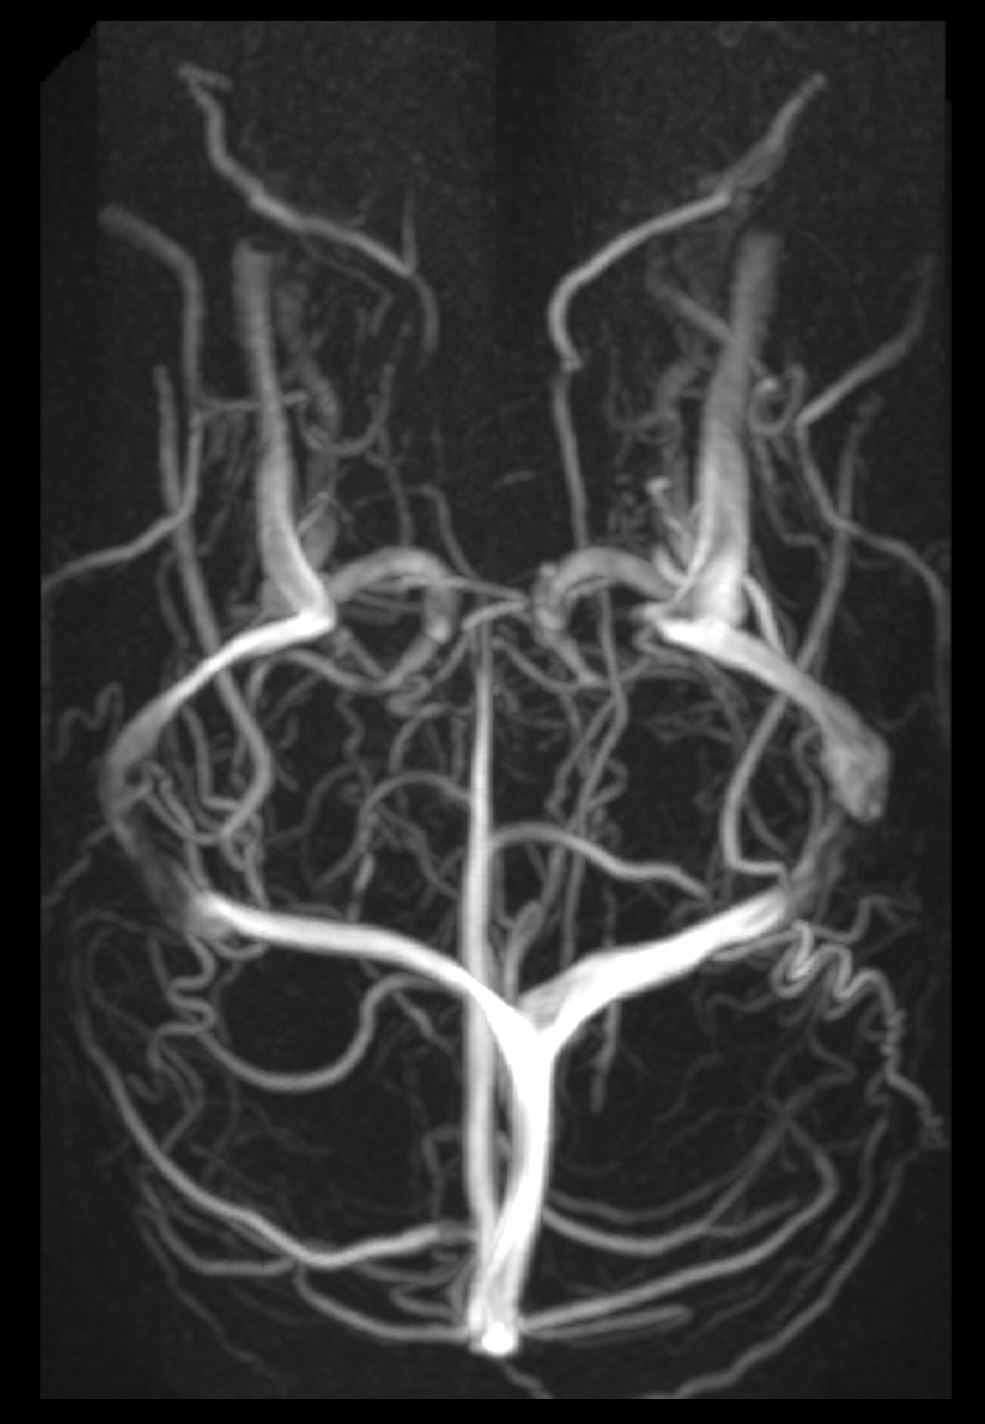

Image IQ Quiz: 25-Year-Old Male with a Headache

What do the images reveal in a 25-year-old male with a headache?